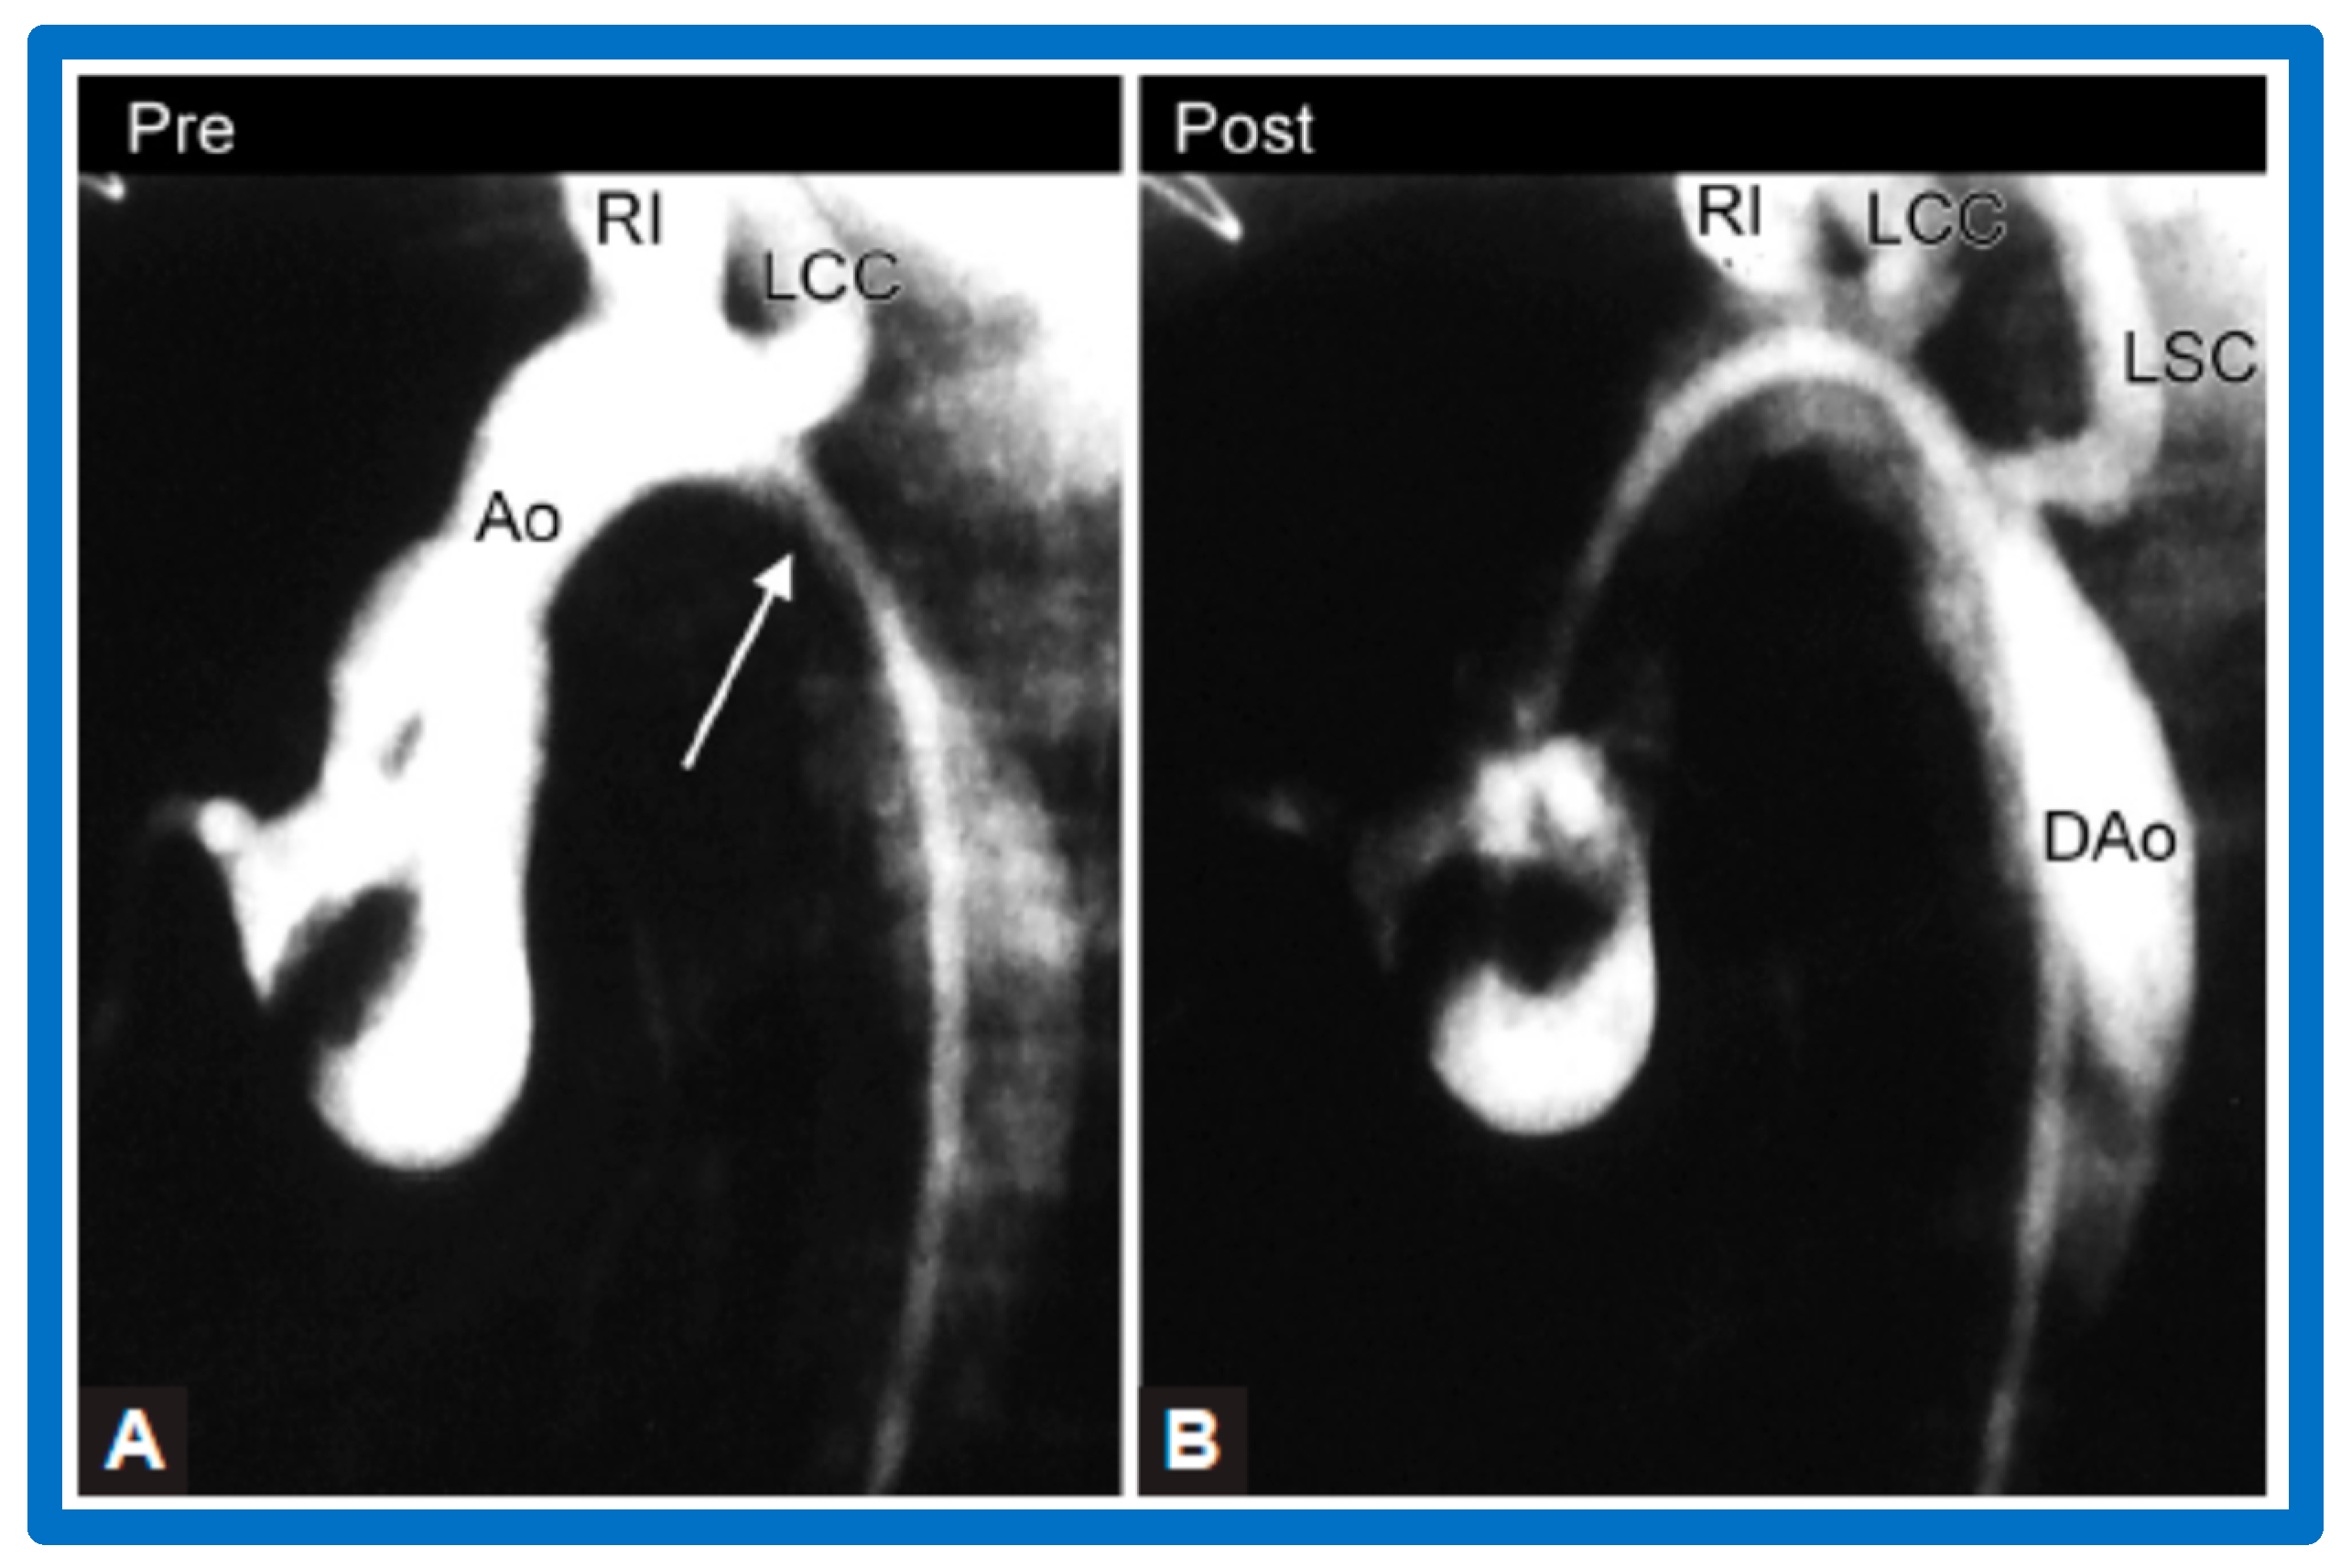

3.3. Aortic Coarctation, Native

4.3. Aortic Coarctation–Native

5.3. Aortic Coarctation–Native

5.3.1. Causes of Restenosis

5.3.2. Feasibility of Repeat BA to Address Recurrence of AC